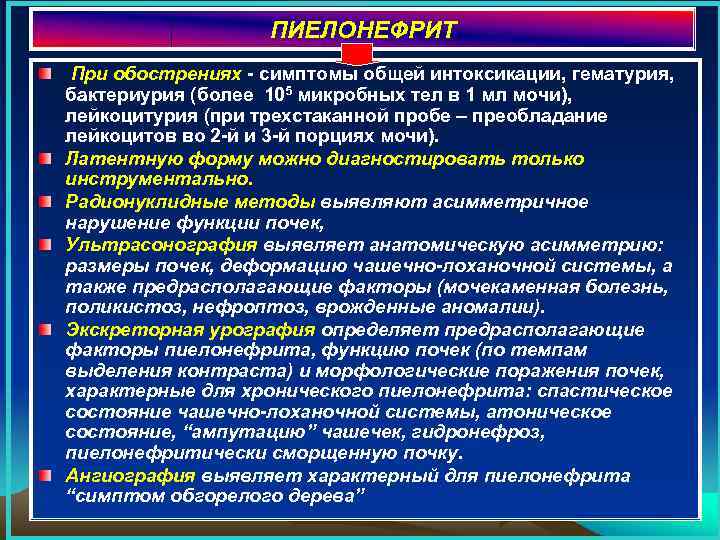

ПИЕЛОНЕФРИТ При обострениях - симптомы общей интоксикации, гематурия, бактериурия (более 105 микробных тел в 1 мл мочи), лейкоцитурия (при трехстаканной пробе – преобладание лейкоцитов во 2 -й и 3 -й порциях мочи). Латентную форму можно диагностировать только инструментально. Радионуклидные методы выявляют асимметричное нарушение функции почек, Ультрасонография выявляет анатомическую асимметрию: размеры почек, деформацию чашечно-лоханочной системы, а также предрасполагающие факторы (мочекаменная болезнь, поликистоз, нефроптоз, врожденные аномалии). Экскреторная урография определяет предрасполагающие факторы пиелонефрита, функцию почек (по темпам выделения контраста) и морфологические поражения почек, характерные для хронического пиелонефрита: спастическое состояние чашечно-лоханочной системы, атоническое состояние, “ампутацию” чашечек, гидронефроз, пиелонефритически сморщенную почку. Ангиография выявляет характерный для пиелонефрита “симптом обгорелого дерева”

ПИЕЛОНЕФРИТ При обострениях - симптомы общей интоксикации, гематурия, бактериурия (более 105 микробных тел в 1 мл мочи), лейкоцитурия (при трехстаканной пробе – преобладание лейкоцитов во 2 -й и 3 -й порциях мочи). Латентную форму можно диагностировать только инструментально. Радионуклидные методы выявляют асимметричное нарушение функции почек, Ультрасонография выявляет анатомическую асимметрию: размеры почек, деформацию чашечно-лоханочной системы, а также предрасполагающие факторы (мочекаменная болезнь, поликистоз, нефроптоз, врожденные аномалии). Экскреторная урография определяет предрасполагающие факторы пиелонефрита, функцию почек (по темпам выделения контраста) и морфологические поражения почек, характерные для хронического пиелонефрита: спастическое состояние чашечно-лоханочной системы, атоническое состояние, “ампутацию” чашечек, гидронефроз, пиелонефритически сморщенную почку. Ангиография выявляет характерный для пиелонефрита “симптом обгорелого дерева”